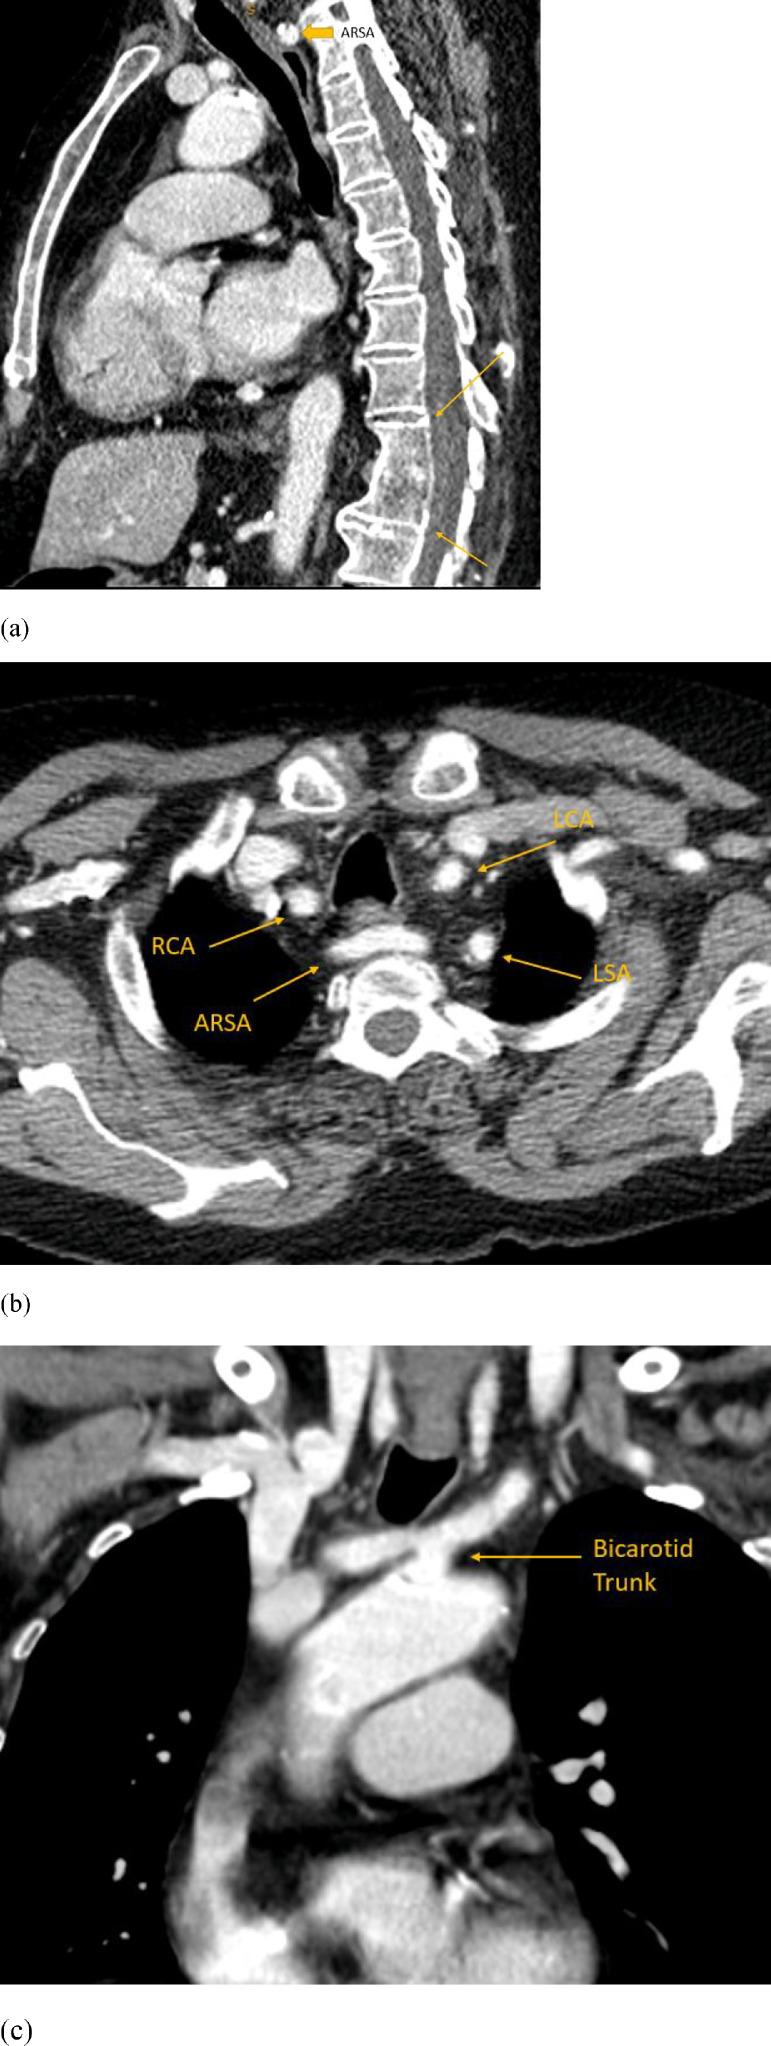

马蹄形肾上腺伴主动脉后右侧膈脚及多种血管变异:2例报告

Horseshoe adrenal gland associated with retro-aortic right diaphragmatic crus and several vascular variants: Report of two cases.

Horseshoe adrenal gland (HA) refers to congenital fusion of the adrenal glands across the midline - a rare anatomical variant often found in association with other congenital anomalies. Here we report 2 cases of HA associated with retro-aortic course of the right diaphragmatic crus, yet another rare anatomical variant, in a 61 your-old male and a 69-year-old female, who underwent CT examinations for unrelated reasons. Both patients also had additional vascular and vertebral anomalies. To the best of our knowledge, this is the first report to document association of 2 rare congenital anomalies: HA and retro-aortic right diaphragmatic crus.

摘要

马蹄形肾上腺(HA)是指肾上腺跨越中线的先天性融合——一种罕见的解剖变异,常与其他先天性异常相关。本文报告2例马蹄形肾上腺合并右膈脚走行于主动脉后方(另一种罕见的解剖变异)的病例,患者分别为一名61岁男性和一名69岁女性,他们因无关原因接受了CT检查。两名患者还存在其他血管和脊柱异常。据我们所知,这是首次报道两种罕见先天性异常:马蹄形肾上腺和右膈脚走行于主动脉后方的关联。